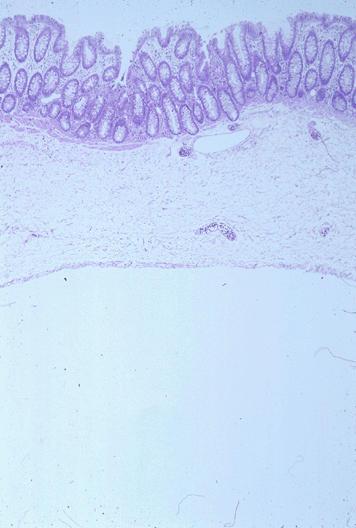

疾患(病理主体)の分類良性非上皮性腫瘍/リンパ管腫

部位(臓器別)大腸/横行

検査方法ミクロ

病変の最大径(ミリ)20〜24